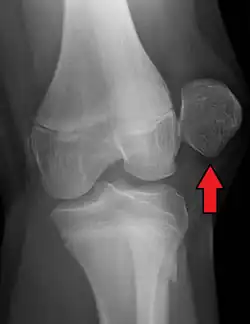

| X-ray showing a patellar dislocation, with the patella out to the side. | |

A patellar dislocation is a knee injury in which the patella (kneecap) slips out of its normal position.[5] Often the knee is partly bent, painful and swollen.[1][2] The patella is also often felt and seen out of place.[1] Complications may include a patella fracture or arthritis.[3]

A patellar dislocation typically occurs when the knee is straight and the lower leg is bent outwards when twisting.[1][2] Occasionally, it occurs when the knee is bent and the patella is struck directly.[1] Commonly associated sports include soccer, gymnastics, and ice hockey.[2] Dislocations nearly always occur away from the midline.[2] Diagnosis is typically based on symptoms and supported by X-rays.[2]

On X-ray, with skyline projections, dislocations are readily diagnosed. In borderline cases of subluxation, the following measurements can be helpful: